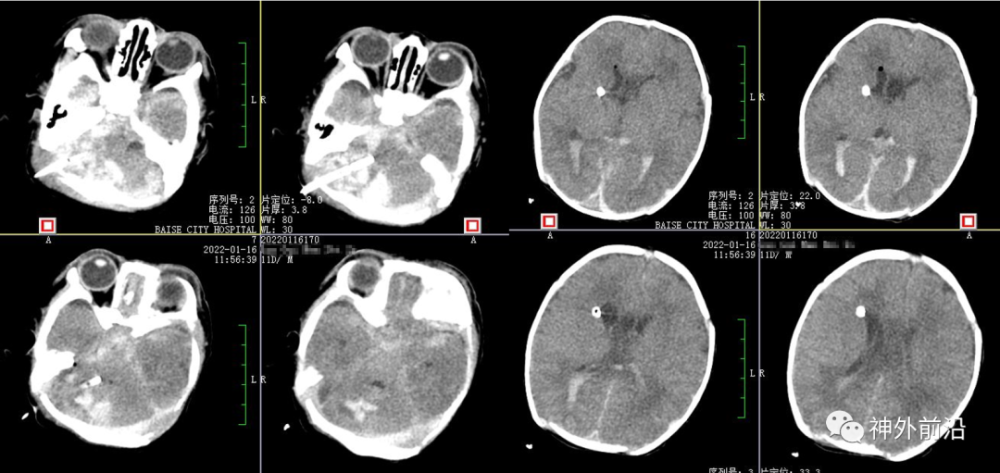

10.术后9天复查CT,拔除侧脑室引流管

11.术后17天复查CT